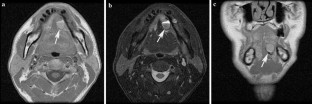

Non-contrast computed tomography and magnetic resonance imaging features of mucoepidermoid carcinoma in the salivary glands

Use of contrast-enhanced cross-sectional imaging is considered standard practice for investigating mucoepidermoid carcinoma (MEC) in the salivary glands. The purpose of this study was to present the common features of MEC on computed tomography (CT) and magnetic resonance imaging (MRI) without contrast enhancements, and to investigate the possibility of discriminating between MEC and pleomorphic adenoma based on the features observed on both modalities.

Twenty cases of biopsy-confirmed MEC originating in the salivary glands were reviewed and characterized by two oral and maxillofacial radiologists with regard to the following aspects: detectability, margin, border, encapsulation, content, contrast between lesion and masticator muscle, and bone changes.

Ninety percent of bone changes caused by MEC were detected by CT and sixty-nine percent of tumor existences were detected by MRI. The lesion border could provide a clue to distinguish MEC from pleomorphic adenoma.

Observation of MEC features was possible by both CT and MRI. Among the features, the lesion border could be a clue to distinguish MEC from pleomorphic adenoma.

Fig. 2